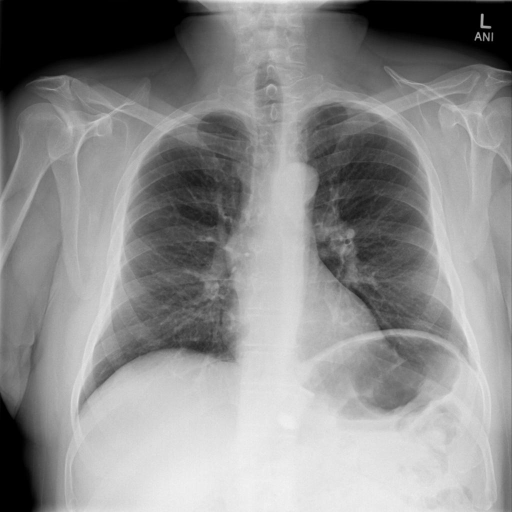

Indiana Dataset [19]: Set consists of 7284 CXRs, both frontal and lateral images with disease annotations, such as cardiomegaly, pulmonary edema, opacity or pleural effusion. Indiana Set is collected from various hospitals affiliated with the Indiana University School of Medicine. The set is publicly available through Open-i SM, which is a multimodal (image + text) biomedical literature search engine developed by U.S. National Library of Medicine. A typical example of a normal CXR (left) and a CXR with cardiomegaly abnormality (right) is shown in Fig. 1. Visually, it can be observed that the heart in the cardiomegaly example is quite big compared to that of the normal CXR.

Figure 1: An example of Normal CXR (left) and an example of a cardiomegaly CXR (right) from Indiana dataset. The pathology in the right CXR can be easily distinguished from the abnormal size and shape of the heart. -